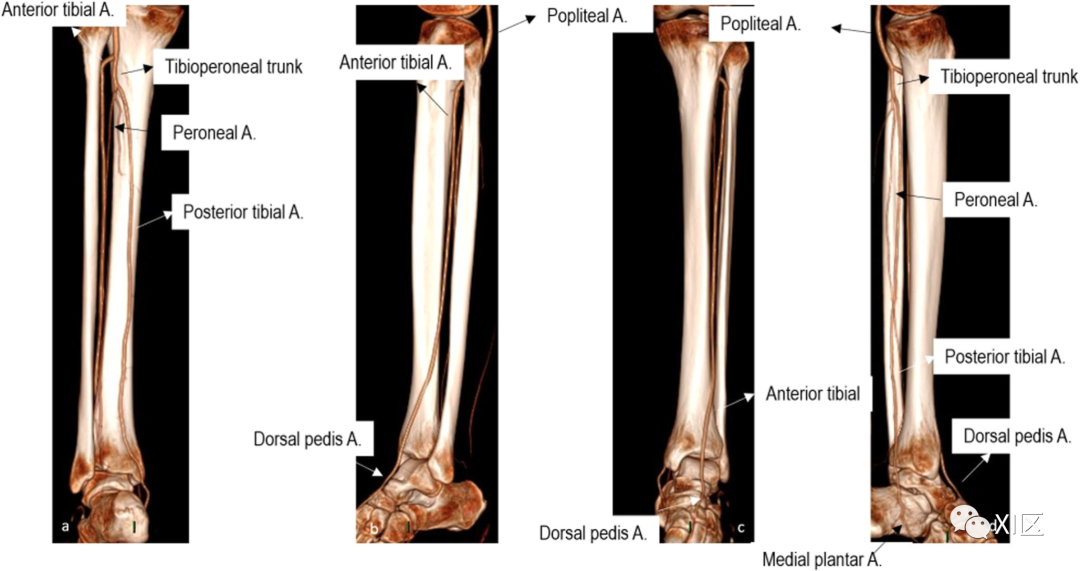

下肢动脉解剖如图1和2所示。

图2 腿部动脉血管解剖CTA的容积再现重建显示了腿部动脉血管区的解剖,包括后视图(a)、侧视图(b)、前视图(c)和内侧视图(d)。